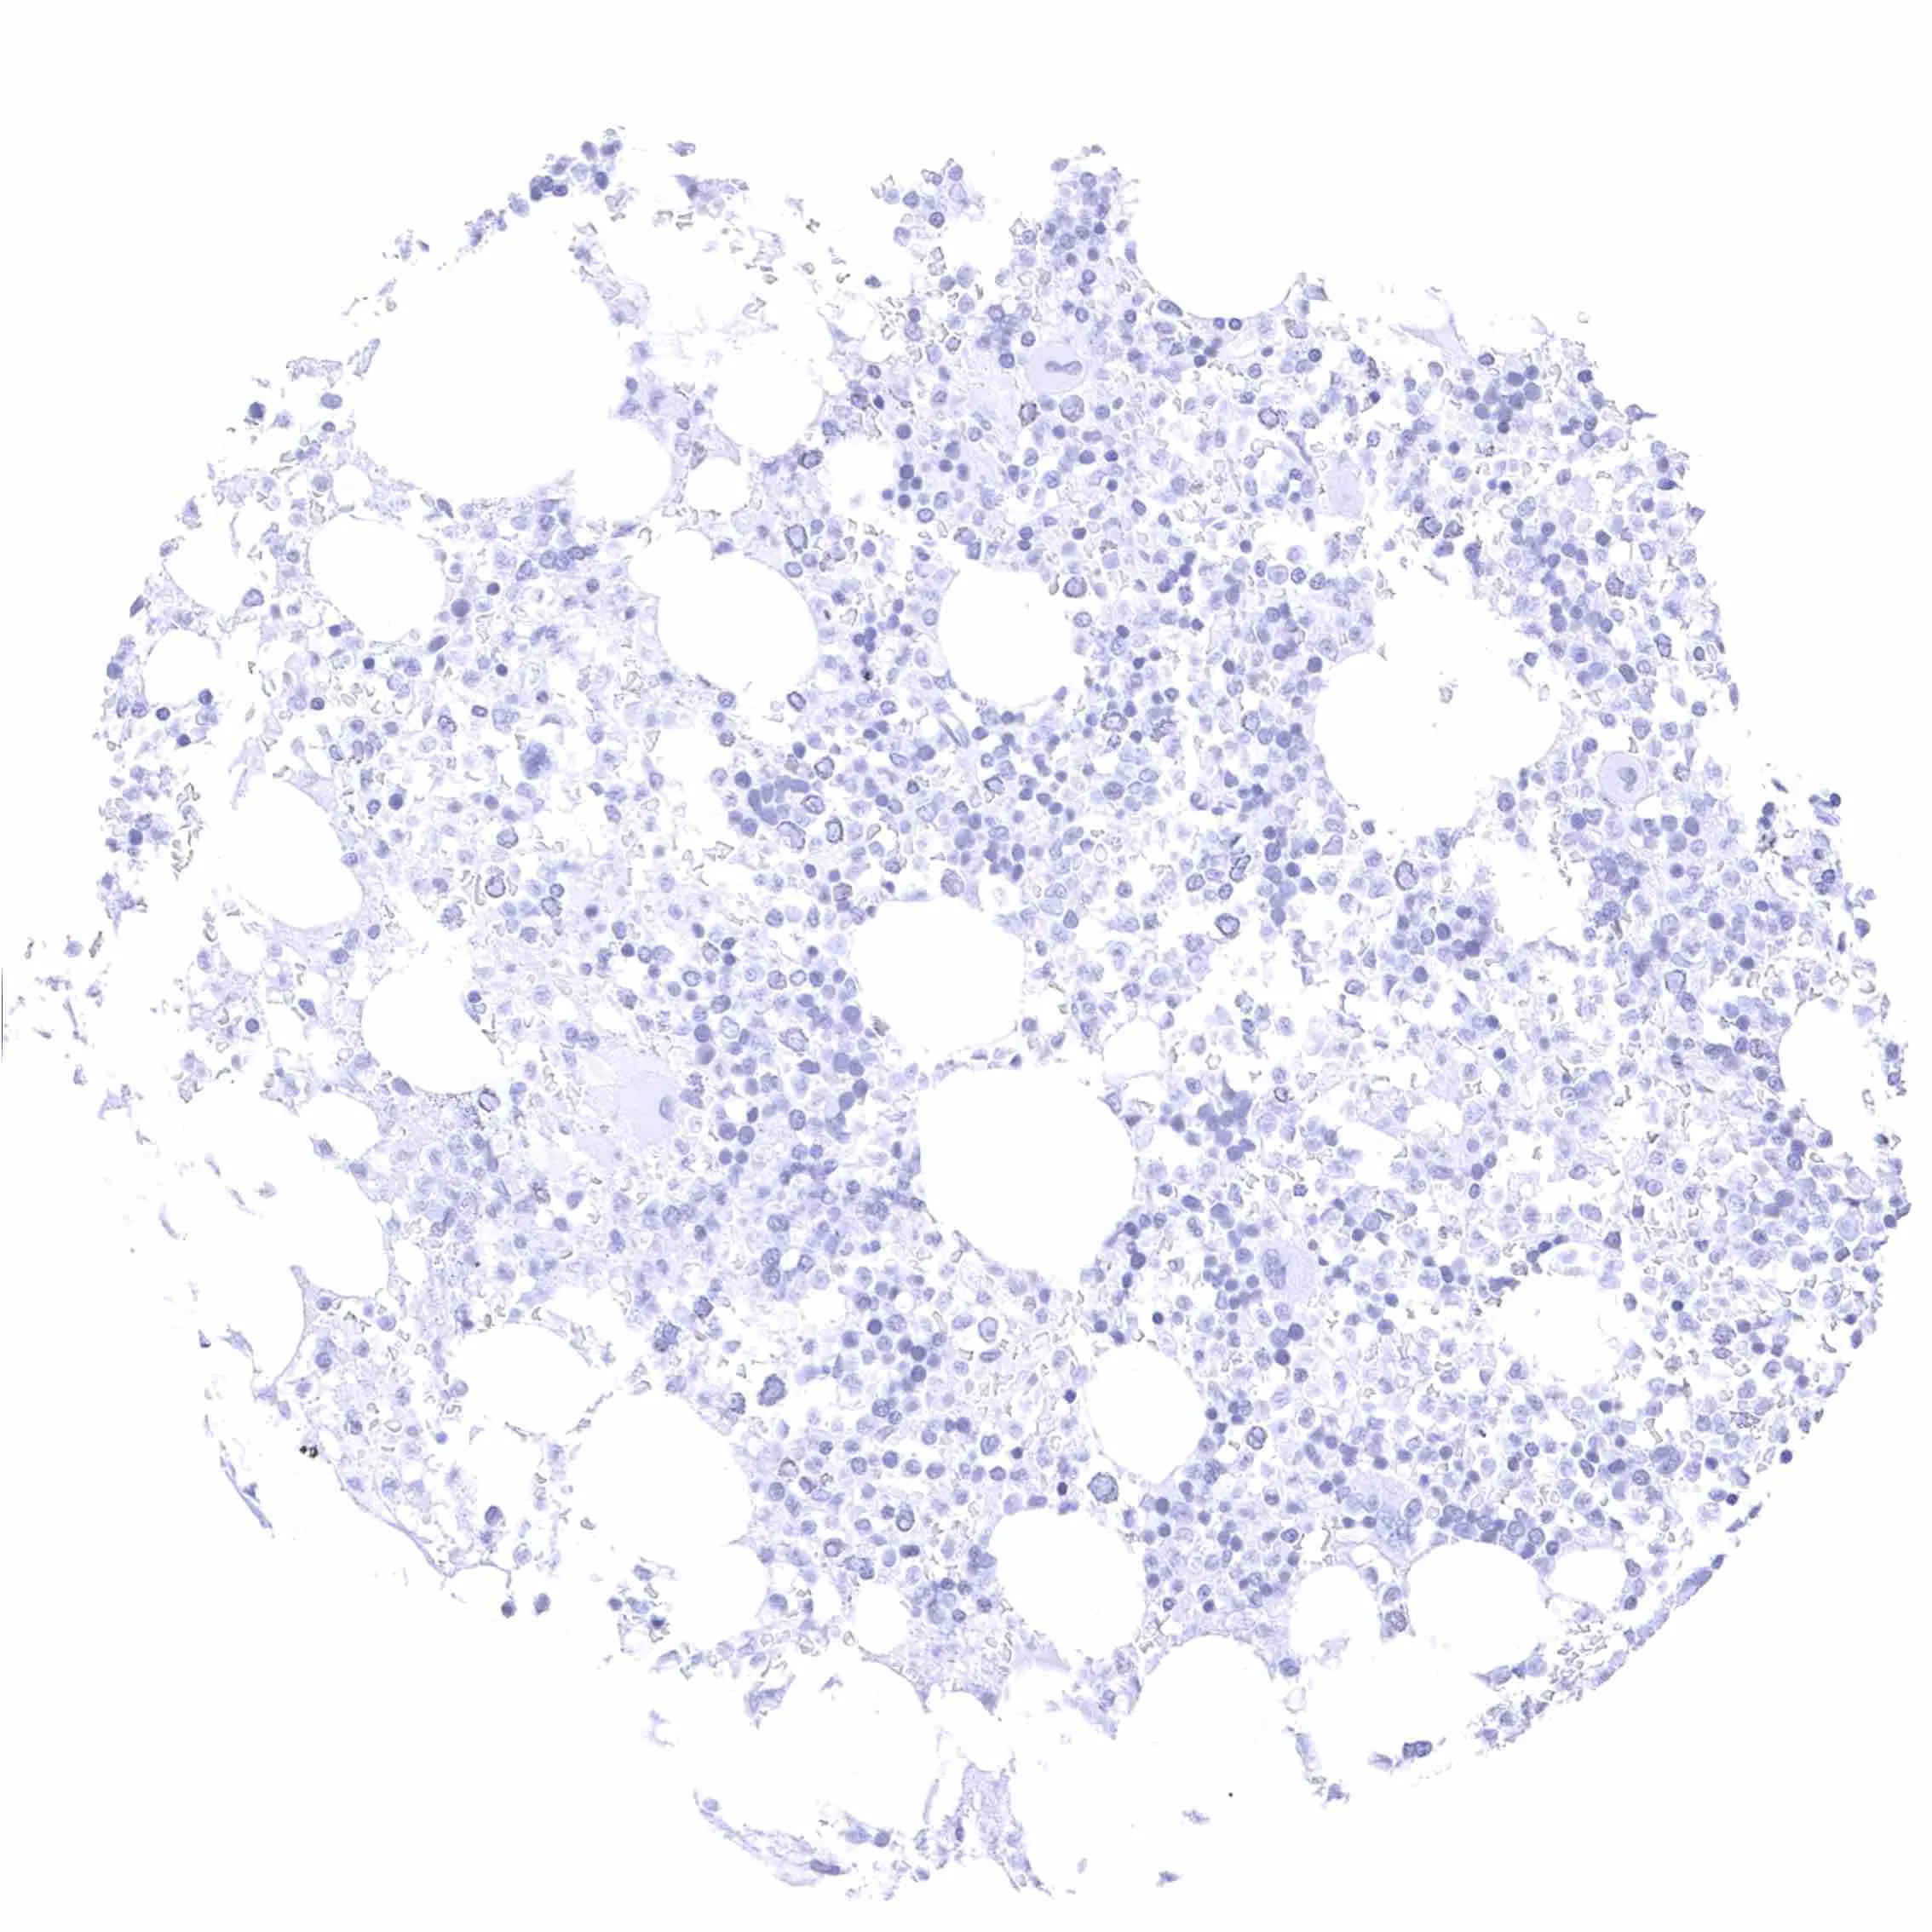

Spleen